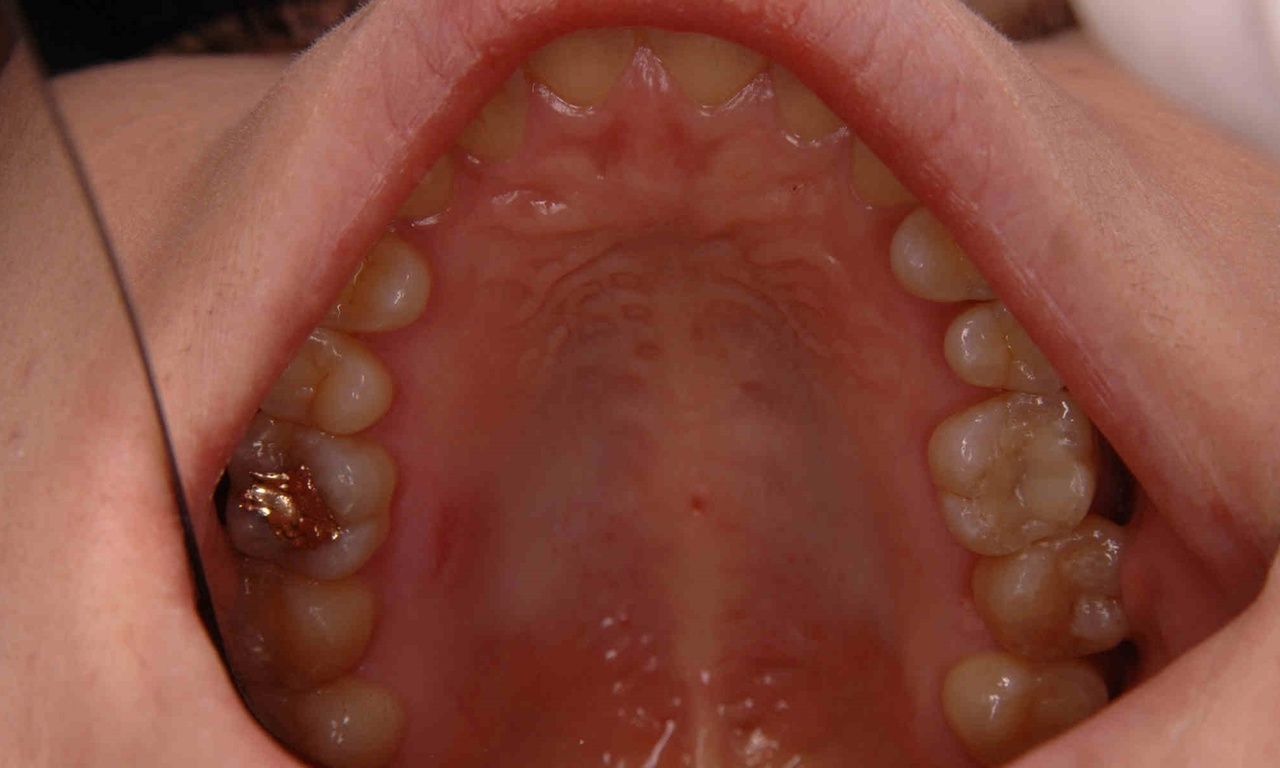

歯へのダメージを減らす【本日の1症例】

右奥歯の大きなむし歯

最小限の範囲で補修